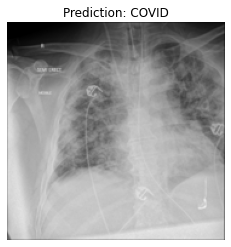

Currently, there is an urgent need for efficient tools to assess the diagnosis of COVID-19 patients. In this project, we propose a constructive solution for detecting and labeling infected tissues on CT lung images of such patients. To cut down false positives our model is trained on 4 types of lung CT images : COVID, Viral Pneumonia, Lung Opacity and normal images to get the best possible results with highest accuracy.

We built it using Tensorflow 2.x using Python. We have developed a Convolutional Neural Network model with an average accuracy of more than 85%. We built the WebApp using Streamlit library for easy interaction with the prediction model.

We are proud that among the top 5 models, one of our models achieved 88.8% accuracy with very low loss.